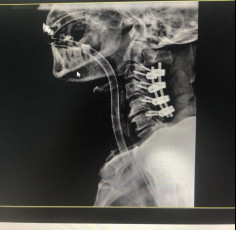

(术后拍片)

今年5月,张阿伯出院近2月后,大部分生活已经可以自理。戈主任为张阿伯做了复查诊治,结果显示他的颈椎固定可靠,复位良好,病体正在朝理想的康复方向发展。